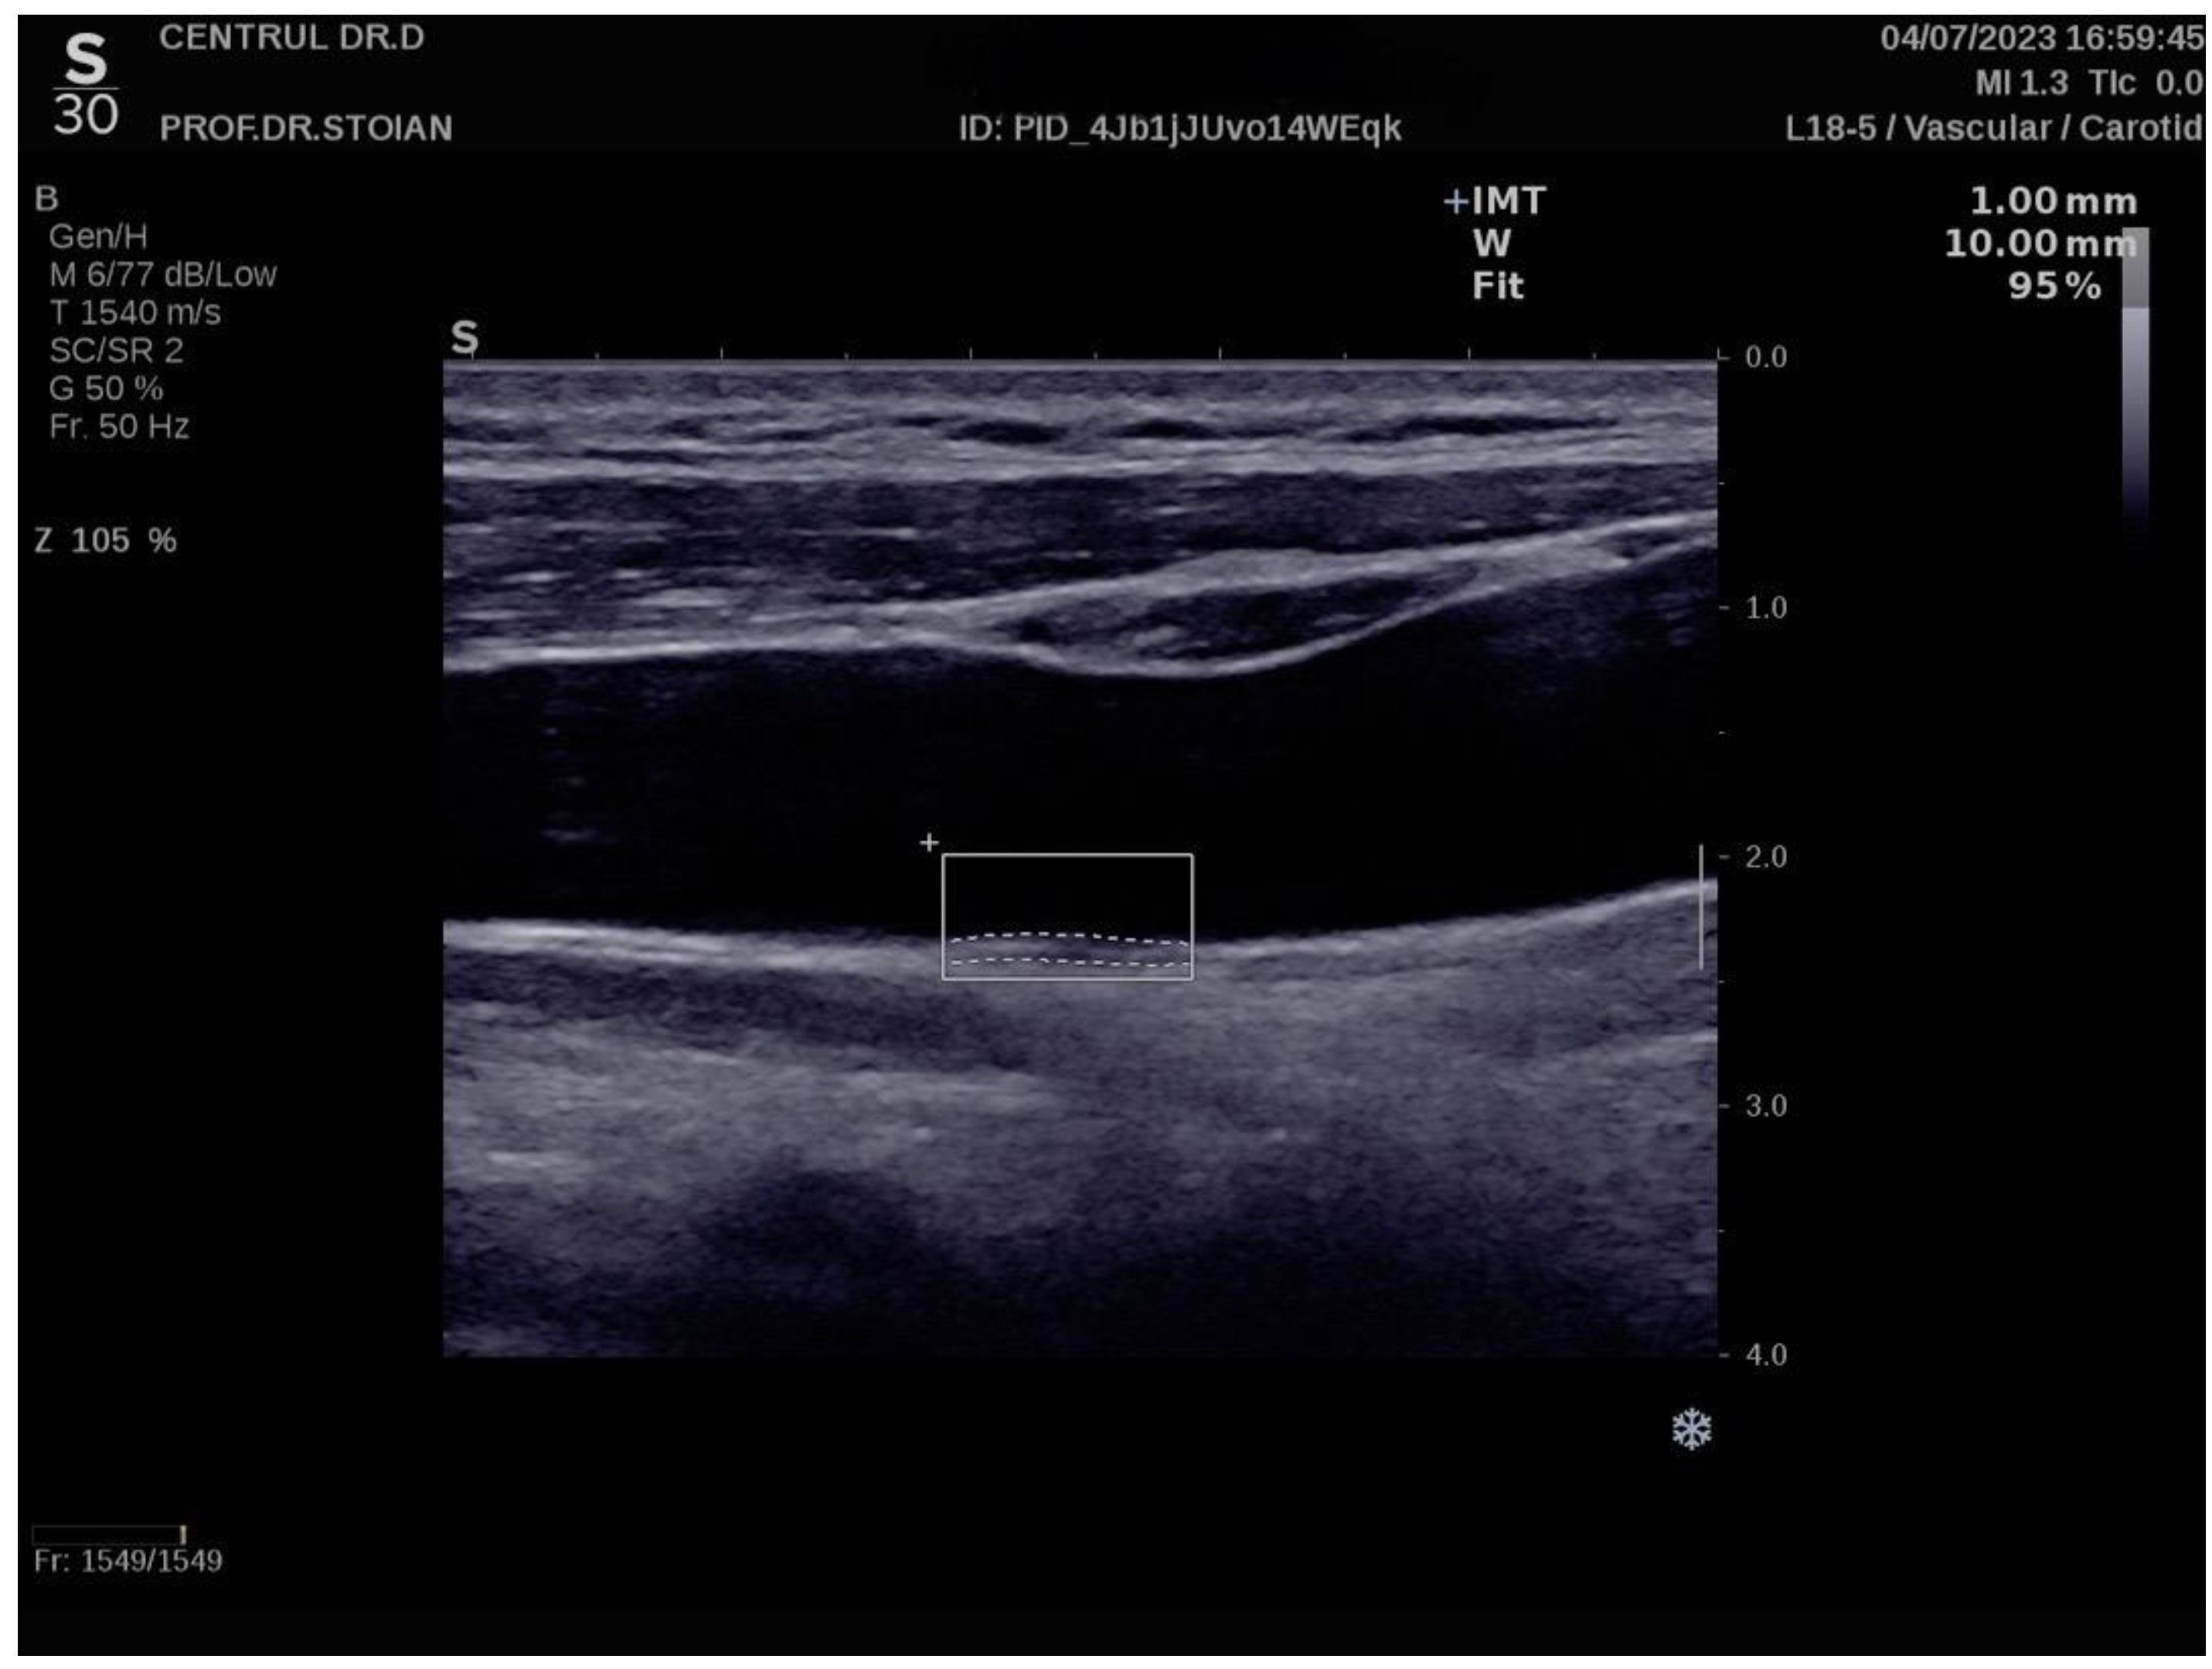

Figure 1 illustrates an example of CIMT evaluation for the left carotid artery obtained using this method in a normoweight subject, whose CIMT value falls within optimal limits. In contrast, Figure 2 depicts an elevated left CIMT value of 1 mm, observed in a patient with grade II obesity. It is important to note that personal data of the evaluated subjects are not displayed to ensure confidentiality.

Example of a normal left CIMT measurement in a normoweight patient using the Aixplorer MACH 30 ultrasound system.

Example of a high value of left CIMT measurement in a subject with obesity grade II using the Aixplorer MACH 30 ultrasound system.